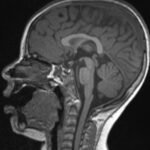

Pediatric neuroblastoma is famously characterized by an abdominal mass in a toddler with “raccoon eyes,” Horner syndrome, and/or opsoclonus myoclonus. However, rare cases may present with non-discrete symptoms and signs which create challenges for timely diagnosis. This case depicts a toddler with bulbar symptoms, including bilateral ptosis, dysphagia, drooling, head tilt and ataxia in a post-viral course mimicking other neurologic diagnoses, including myasthenia gravis. Magnetic resonance imaging (MRI) of the brain and spine uncovered a right adrenal mass along with heterogenous enhancement in multiple vertebral bodies and the clivus, consistent with metastatic disease. A diagnosis of neuroblastoma was confirmed with elevated homovanillic acid (HMA) and vanillylmandelic acid (VMA) levels and adrenal biopsy. The patient was treated with plasmapheresis for suspected paraneoplastic neurological syndrome and subsequent chemotherapy. In this case presentation, we review neurologic syndromes causing acute-onset pediatric bulbar weakness along with the patient’s key MRI findings.